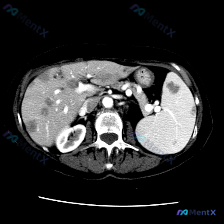

最近看到一份很有警示意义的腹部增强CT资料,整理一下思路和大家分享。 先看影像核心表现 这份是上腹部增强CT横断面软组织窗,主要异常集中在肝脏和脾脏: 1. 脾脏:体积稍大,脾实质内可见多发类圆形低密度结节灶,边界清晰,部分病灶边缘可见强化,呈「靶征」或「环形强化」改变。 2. 肝脏:肝实质内也可见...

整理了一份肝脾同时出现多发占位的影像及鉴别思路,分享给大家。 --- 先看影像核心发现 这是一张增强腹部CT横断面(软组织窗): 1. 肝脏:肝左右叶弥漫分布多发、大小不一类圆形低密度灶,边缘相对清晰,部分病灶可见边缘强化/“靶征”; 2. 脾脏:脾脏实质内也有类似的低密度占位病变; 3. 其他:腹...